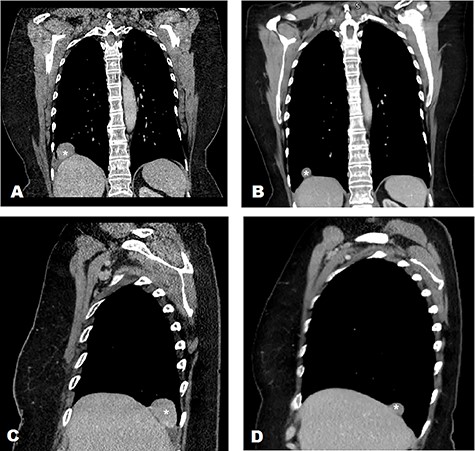

A 65-year-old female, with a background history of breast cancer, presented with dysphagia. Physical examination was unremarkable. Computed tomography (CT) scan of neck and thorax (Fig. 1) revealed a 4.2 cm supradiaphragmatic pleural-based mass. This had gradually enlarged over the preceding 2 years (original size 1.7 cm) and was reported as suspicious of pleural fibroma. Subsequent positron emission tomography (PET) scan (Fig. 2) revealed a smooth, mildly avid peripheral/pleural-based 4.2 cm right lower lobe lung mass with a maximum standardized uptake value (SUVmax) of 4.3, contiguous with the right hemidiaphragm. Multidisciplinary team meetings were held, and the experts concluded that there was a clear cleavage plane between the slow growing mass and liver. The mass was thought to represent a solitary fibrous pleural tumour, and hence the decision for resection was made.

CT characterisation of supradiaphragmatic mass in 2 different views (mass marked with ‘*’) demonstrating a clear cleavage plane separating the mass and liver in 2020 and 2018. (A) CT scan of thorax in 2020—coronal view. (B) CT scan of thorax in 2018—coronal view. (C) CT scan of thorax in 2020—sagittal view of right hemithorax. (D) CT scan of thorax in 2018—sagittal view of right hemithorax.